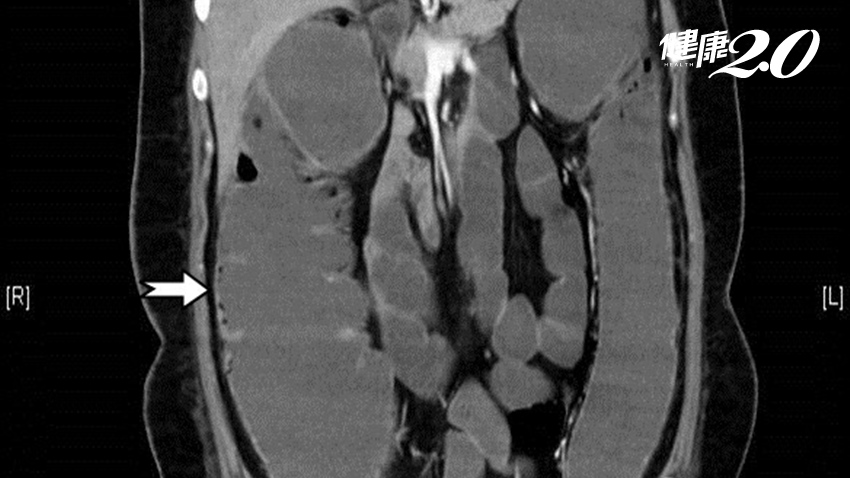

高雄長庚醫院大腸直腸外科主治醫師蔡鎧隆指出,女子到院時血壓不穩、肚子觸感很硬,立即為其採集檢體與安排電腦斷層檢查,發現大腸腫脹是正常人的2倍,隨即安排開刀房進行手術,果真發現女子九成以上的大腸發黑、壞死,且已併發毒性巨結腸症與敗血症,為求保命前提下,切除壞死約100公分的大腸,並做一個腸造口。

▲由影像中箭頭處,可明顯看出腸子腫脹嚴重。

毒性巨結腸症會使腸道蠕動變慢,甚至不蠕動,持續堆積毒素下,接著可能併發腸壞死與腸穿孔或敗血症等高致死性併發症。